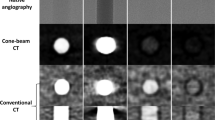

Visualisation of vehicle and microsphere distributions by synchrotron x-ray micro computed tomography

Microspheres detected in the reconstructed μCT data were 3–4 pixels in diameter as a function of their size and image resolution, and exhibited varying visibility depending on the acquisition noise levels. Those microspheres deposited in a vehicle spiked with contrast agent were found to have brighter pixel values corresponding to higher attenuation levels, presumably as a consequence of contrast agent surface-adsorption (Fig. 3). Samples injected with aqueous vehicle in combination with the contrast agent gave a much more diffuse contrast than the nonaqueous vehicle meaning that tissue regions with low vehicle concentration were less visible.

In the absence of contrast agent, microspheres were detected albeit with reduced sensitivity.

Weakly X-ray absorbing and at a length scale marginally greater than the resolution of the system, the microspheres presented some challenges in automating image analysis. Material segmentation was not possible with intensity thresholding alone. However, it was possible to exploit the additional higher spatial frequencies within the unfiltered images due to the component of edge enhancement present, and consistent particle morphology, with a texture based custom thresholding method. When combined with intensity thresholding it was possible to significantly both increase the true positives and reduce the false positives of detected microspheres in the subcutis. Embedding the tissue samples in agarose made automatic segmentation challenging due to lack of density difference between the agarose and porcine tissue. Follow-up experiments, where samples were not embedded in agarose, significantly improved this process with no detrimental impact on data quality.

During optimisation of tomographic image acquisition, the utility of Module 1 and the LFV module for the in-situ imaging of microspheres and vehicle was explored. The application of LFV module was considered since larger tissue sections can be imaged with the caveat of a lower resolution image being obtained. Overall, images generated from Module 1 were found to offer superior contrast and resolution with the capability to probe microsphere localisation when compared to the LFV setup.

Lab-based CT has previously been utilised to visualise and quantify spatial distribution of soluble insulin formulations [26, 27]. We selected synchrotron μCT for these experiments because with an effective voxel size of 50 μm and resolution of 120 μm, resolution of microspheres in the 20–100 μm size range could not be achieved with conventional lab-based CT. Furthermore, the image acquisition time for lab-based CT is significantly longer for the tissue section sizes investigated in this study (45 min versus 50 or 150 s). The resolution of the technique reported here enabled the detection of individual deposited PLG microspheres (20–100 μm diameter) within ex vivo porcine tissue, and visualization of subcutaneously- injected microsphere suspension fate.

A component of the PLG microsphere visibility may be attributed to the additional phase contrast present (edge enhancement- where each material interface is highlighted by a local intensity minimum directly adjacent to the maximum). This is one of the several advantages of using a synchrotron X-Ray source for the CT (other advantages include improved contrast from the smaller energy bandwidth, shorter acquisition times possible due to higher photon flux, etc).